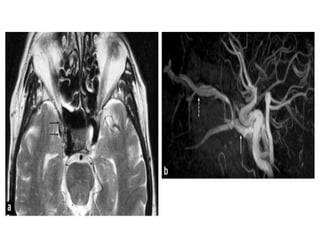

Aneurysms

The diagnosis of aneurysms is critically important in a sellar region

evaluation.

The arteries in the Willis´ polygon, which surrounds the sella turcica, are

the most frequent locations of intracranial aneurysms.

A round lesion with an internal signal void on spin echo MRI, especially

on those acquired with T2WI is a classic feature of an aneurysm with

rapid internal blood flow.

However, partially thrombosed aneurysms appear as well demarcated

round parasellar or intra-sellar lesions with internal T1WI hyperintensity

and characteristic heterogeneous T2WI hypointensity, findings that

indicate intra-aneurysmal clotting.

A giant aneurysm with partial internal clotting may mimic a solid

destructive tumor of the skull base, so MR angiography or

conventional angiography should be performed in cases with these

features before biopsy is considered.

The finding of a residual patent lumen on images helps confirm the

diagnosis of aneurysm.

• #7 Aneurysm: axial T2-wi (a) shows a heterogeneous and enlarged right cavernous sinus with a multilayer appearance (black arrows) corresponding to a giant intracavernous aneurysm. Note the mass effect on the right temporal lobe. See also the 3D volume rendering showing the aneurysm (b).

• #9 Right posterior communicating artery aneurysm digital angiography and MR.

• #10 Intracavernous aneurysms. A, Axial T2-weighted image shows a left intracavernous ICA (A) aneurysm. Note flow artifacts (arrow) confirming the pulsatile nature of the lesions. B, Coronal postcontrast maximum-intensity image from a CT angiogram in the same patient shows the left intracavernous aneurysm.